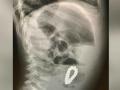

धक्कादायक! 4 वर्षीय मुलाच्या पोटात सापडलं मॅग्नेटिक ब्रेसलेट, एक्स-रे पाहून डॉक्टरही हैराण - Marathi News | boy swallow magnetic bracelet 4 year old complains of stomach pain doctors find magnetic bracelet inside | Latest national News at Lokmat.com

राष्ट्रीय :धक्कादायक! 4 वर्षीय मुलाच्या पोटात सापडलं मॅग्नेटिक ब्रेसलेट, एक्स-रे पाहून डॉक्टरही हैराण

एका 4 वर्षीय मुलाच्या पोटात चक्क मॅग्नेटिक ब्रेसलेट सापडलं. एक्स-रे पाहून डॉक्टरही हैराण झाले आहेत. ...